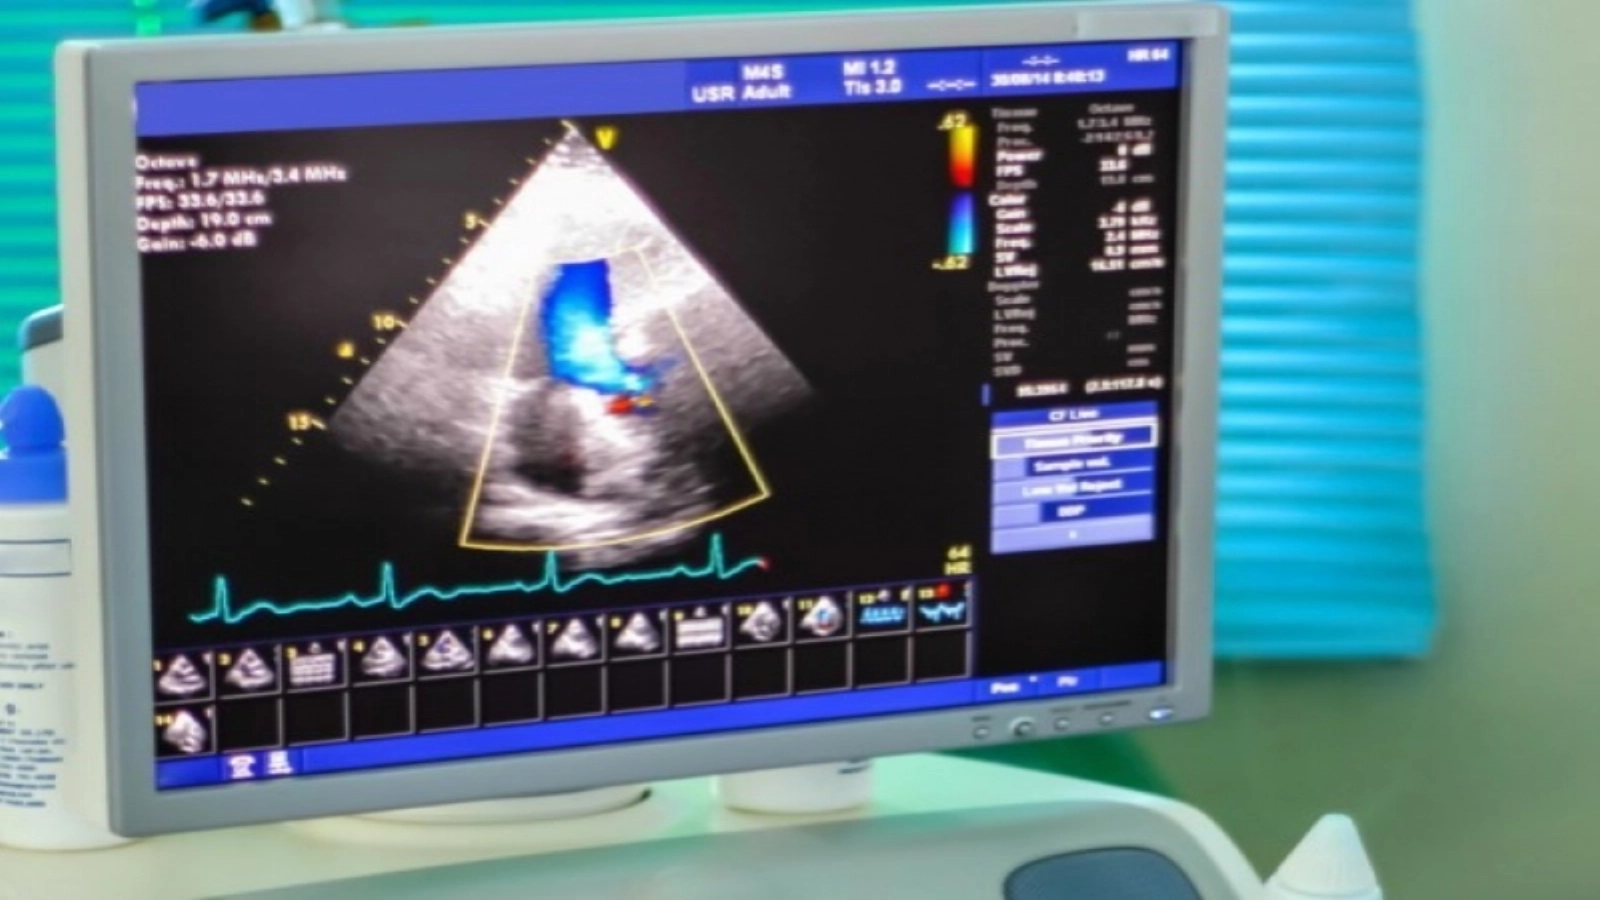

Ecocardiografia (ecografia cardiacă) este una dintre cele mai folosite metode imagistice prin care este evaluat cordul, fiind o procedură neiradiantă și neinvazivă. Aceasta furnizează cu acuratețe informații atât despre structura, cât și despre funcția inimii. Ecocardiografia se realizează cu ajutorul unui transductor ce emite și captează ultrasunete și care se poziționează fie pe toracele pacientului, în cazul ecografiei transtoracice, fie în interiorul esofagului, în cazul ecografiei transesofagiene.

Ecografia transesofagiană are avantajul obținerii unor imagini de calitate superioară a structurilor cordului datorită lipsei interpunerii structurilor care afectează calitatea imaginii transtoracice, precum plămânul sau țesutul adipos.